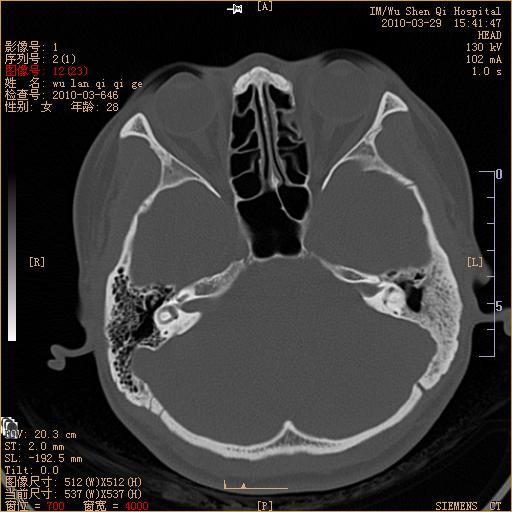

标题: CT25398:女,左耳流脓两年余,带有异物 [打印本页]

标题: CT25398:女,左耳流脓两年余,带有异物

左侧中耳乳突炎,不排除胆脂瘤形成。

左侧中耳乳突炎,胆脂瘤形成。

1)左侧慢性中耳乳突炎并肉芽肿(或胆脂瘤)形成。2)考虑左侧颞骨慢性炎症伴骨质增生硬化,不排除骨纤。